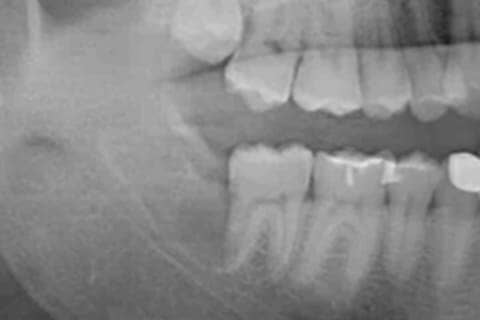

Step6

レントゲン撮影やCT撮影

詳しいお口の状態などを調べるため、レントゲン・CTスキャンを撮影させていただきます。